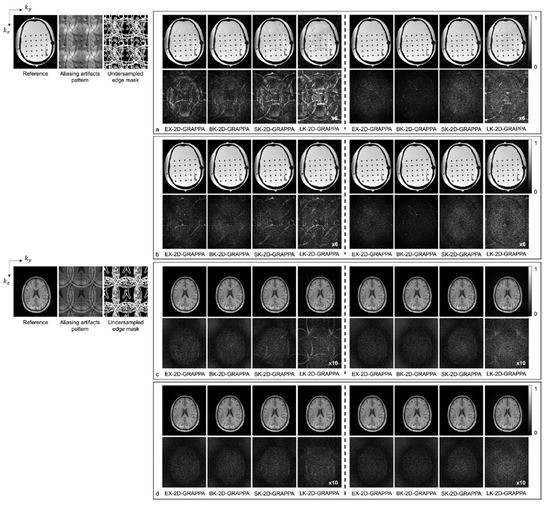

3. Materials and Methods

4. Results